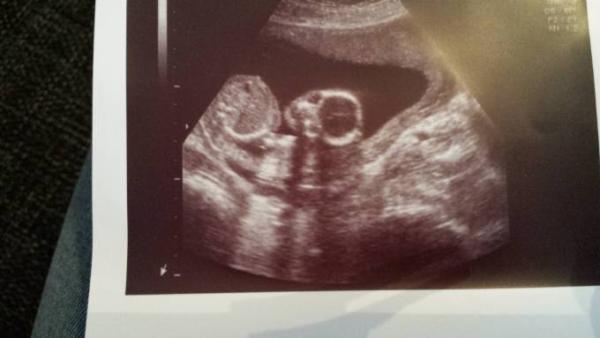

Hier auch ein Bildchen